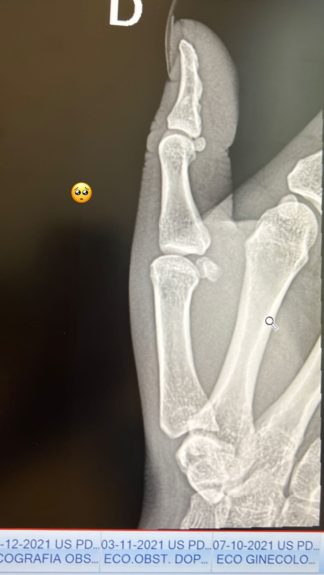

En la jornada de este miércoles, la cubana mostró una serie de registros de su lesión en el pulgar, el cual tendría una duración de tres semanas. “Ando un poco desanimada, con unos moretones alucinantes, adolorida”, dijo en una de sus stories.

“Resultó ser un esguince, que, si bien no es nada grave, igual duele mucho, no puedo mover el dedo, entonces, todo lo que es agarre me cuesta, así que me lo inmovilizaron”, añadió.

Con respecto al momento del percance, la exchica reality mencionó: “Este fue un pequeño accidente que sufrimos bailando el domingo con Gianfranco, no fue culpa de él, me caí sin querer y todo mi peso fue hacia el dedo, grité como no se imaginan, de hecho, pensé que se me había roto el dedo”.